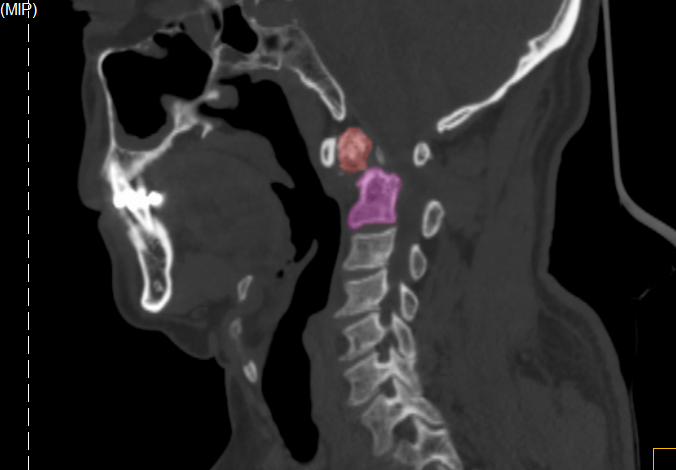

張奶奶術后CT

術后第2天,老人就佩戴頸椎支具下床活動。目前,張奶奶病情恢復良好,穩步康復中。